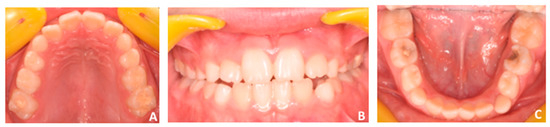

2.1. Patient’s Clinical Characteristics

2.4. Diagnosis and Treatment Plan